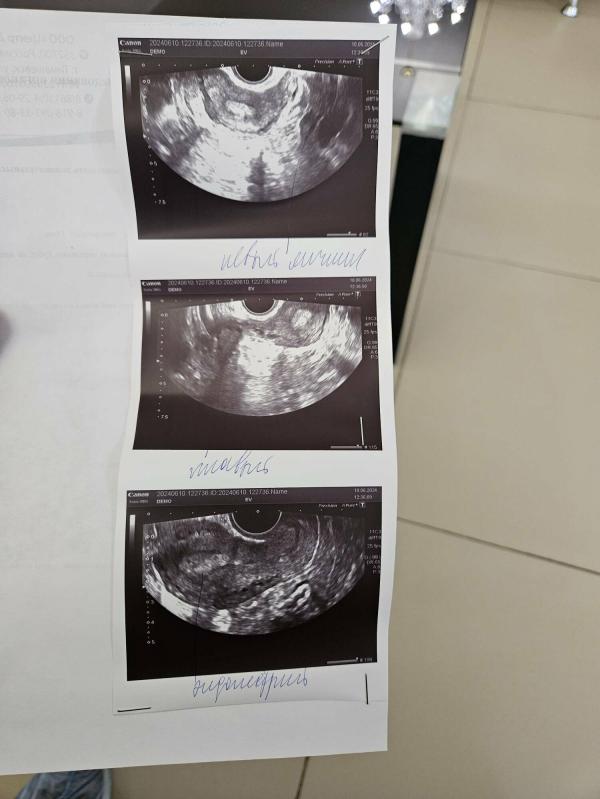

Не факт. Сдайте хгч в динамике.Повторите узи через неделю.

Вот сижу жду , сейчас пойду сдам кровь, а там посмотрим по факту

Рано в 5 недель

Сдавать хгч и ждать 7-8 нед